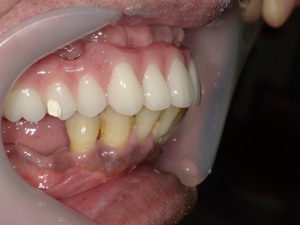

前歯に連結固定した差し歯が入っています。おそらく奥歯がなりなり、噛めなくなるので、前歯でしっかり噛めるように連結固定したのだと思いますが・・

治療前の写真です。前歯がぐらぐらになっています

奥歯がなくなり、前歯ばかりで噛んでいるとフレアーアウトといって前歯がどんどん前に傾いて出てきます。

術後の写真です。フレアーアウトした分、歯を引っ込めてかみ合わせも若干高くしています。

術前の口元と別人になっているのが分かると思います。